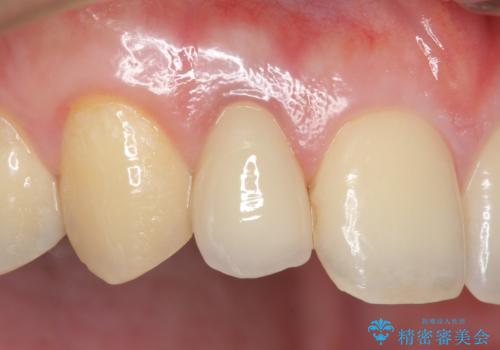

- 冷たいものを飲むと右上の奥歯がしみるので診て欲しいといらっしゃった方の症例です。

右上6番目、7番目の歯の樹脂が劣化していたため、虫歯除去後セラミックインレーによる修復を行いました。

当院のセラミックインレーはemaxという強度と審美性に優れた材料を使用しています。

またプレス方式でインレーを製作しているため、削り出しで製作するCADCAMより優れた適合性も持ち合わせており、虫歯が再発しにくい修復物です。